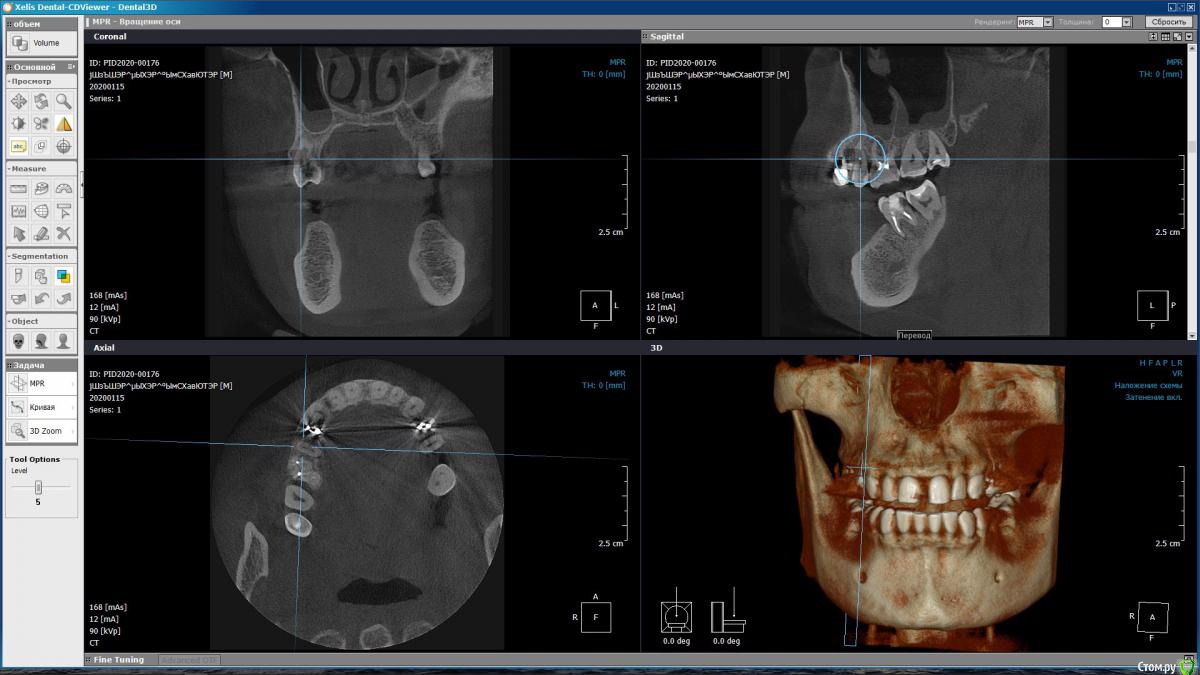

m-e-a Опубликовано 19 января, 2020 Автор Поделиться Опубликовано 19 января, 2020 (изменено) Сделала срезы как смогла, не умею я смотреть КТ Изменено 19 января, 2020 пользователем m-e-a Ссылка на комментарий

red_butler Опубликовано 19 января, 2020 Поделиться Опубликовано 19 января, 2020 На представленных срезах, показаний к удалению не увидел. Нужно смотреть очно и «крутить» Кт Ссылка на комментарий